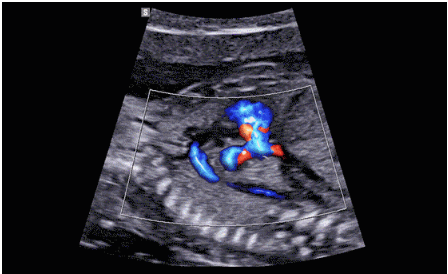

CrystalLive?是三星最新的超聲成像引擎,同時(shí)增強(qiáng)了2D圖像處理能力、3D渲染能力和彩色信號(hào)處理能力,能夠在復(fù)雜情況下提供出色的圖像性能,具備檢測外周血管、微循環(huán)血流的能力。